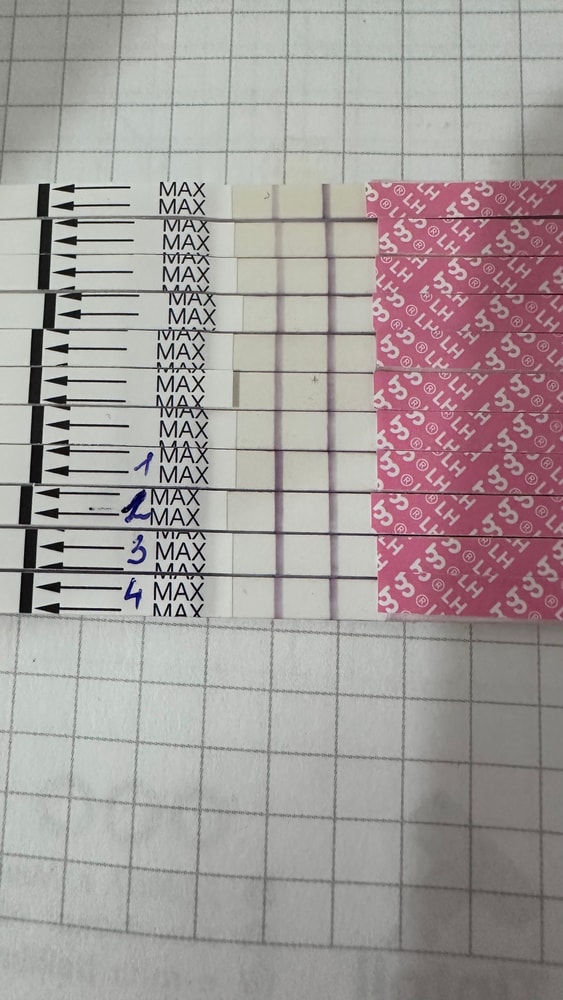

Собрала тесты с цикла в коробку, как всегда😩

Вышла из дисперсии очередной неудачи…заказала тесты, уже в пути…ведь тестов много не бывает, уж я то знаю, спустя столько л